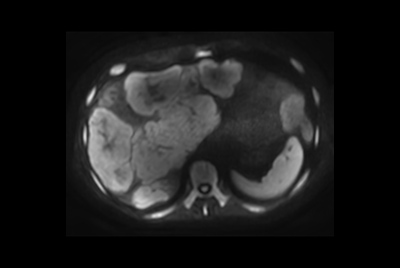

Kidney imaging – Free breathing